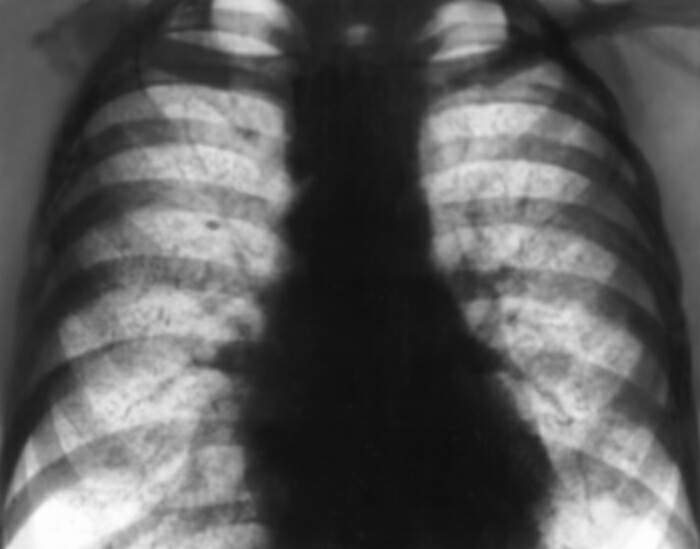

Рентгенограмма органов грудной клетки при идиопатическом гемосидерозе легких

В начале болезни диагноз представляет определенные трудности. Исследование мокроты или рвотных масс обнаруживает наличие гемосидерофагов. Па рентгенограмме грудной клетки определяются небольшие инфильтраты или массивные поражения с вторичными ателектазами, эмфиземой и увеличением прикорневых лимфатических узлов. Достоверный прижизненный диагноз возможен только при открытой или пункционной биопсии легкого.